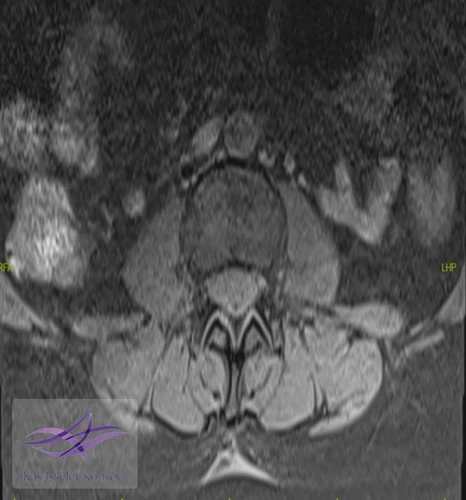

Resim 2. Aksiyel T2 ağırlıklı MR görüntülerinde lezyon paraspinal kas düzlemlerinden net bir şekilde ayrılarak deri altı doku ile fasyal tabaka arasında iyi sınırlı bir sıvı sinyal alanı mevcut.